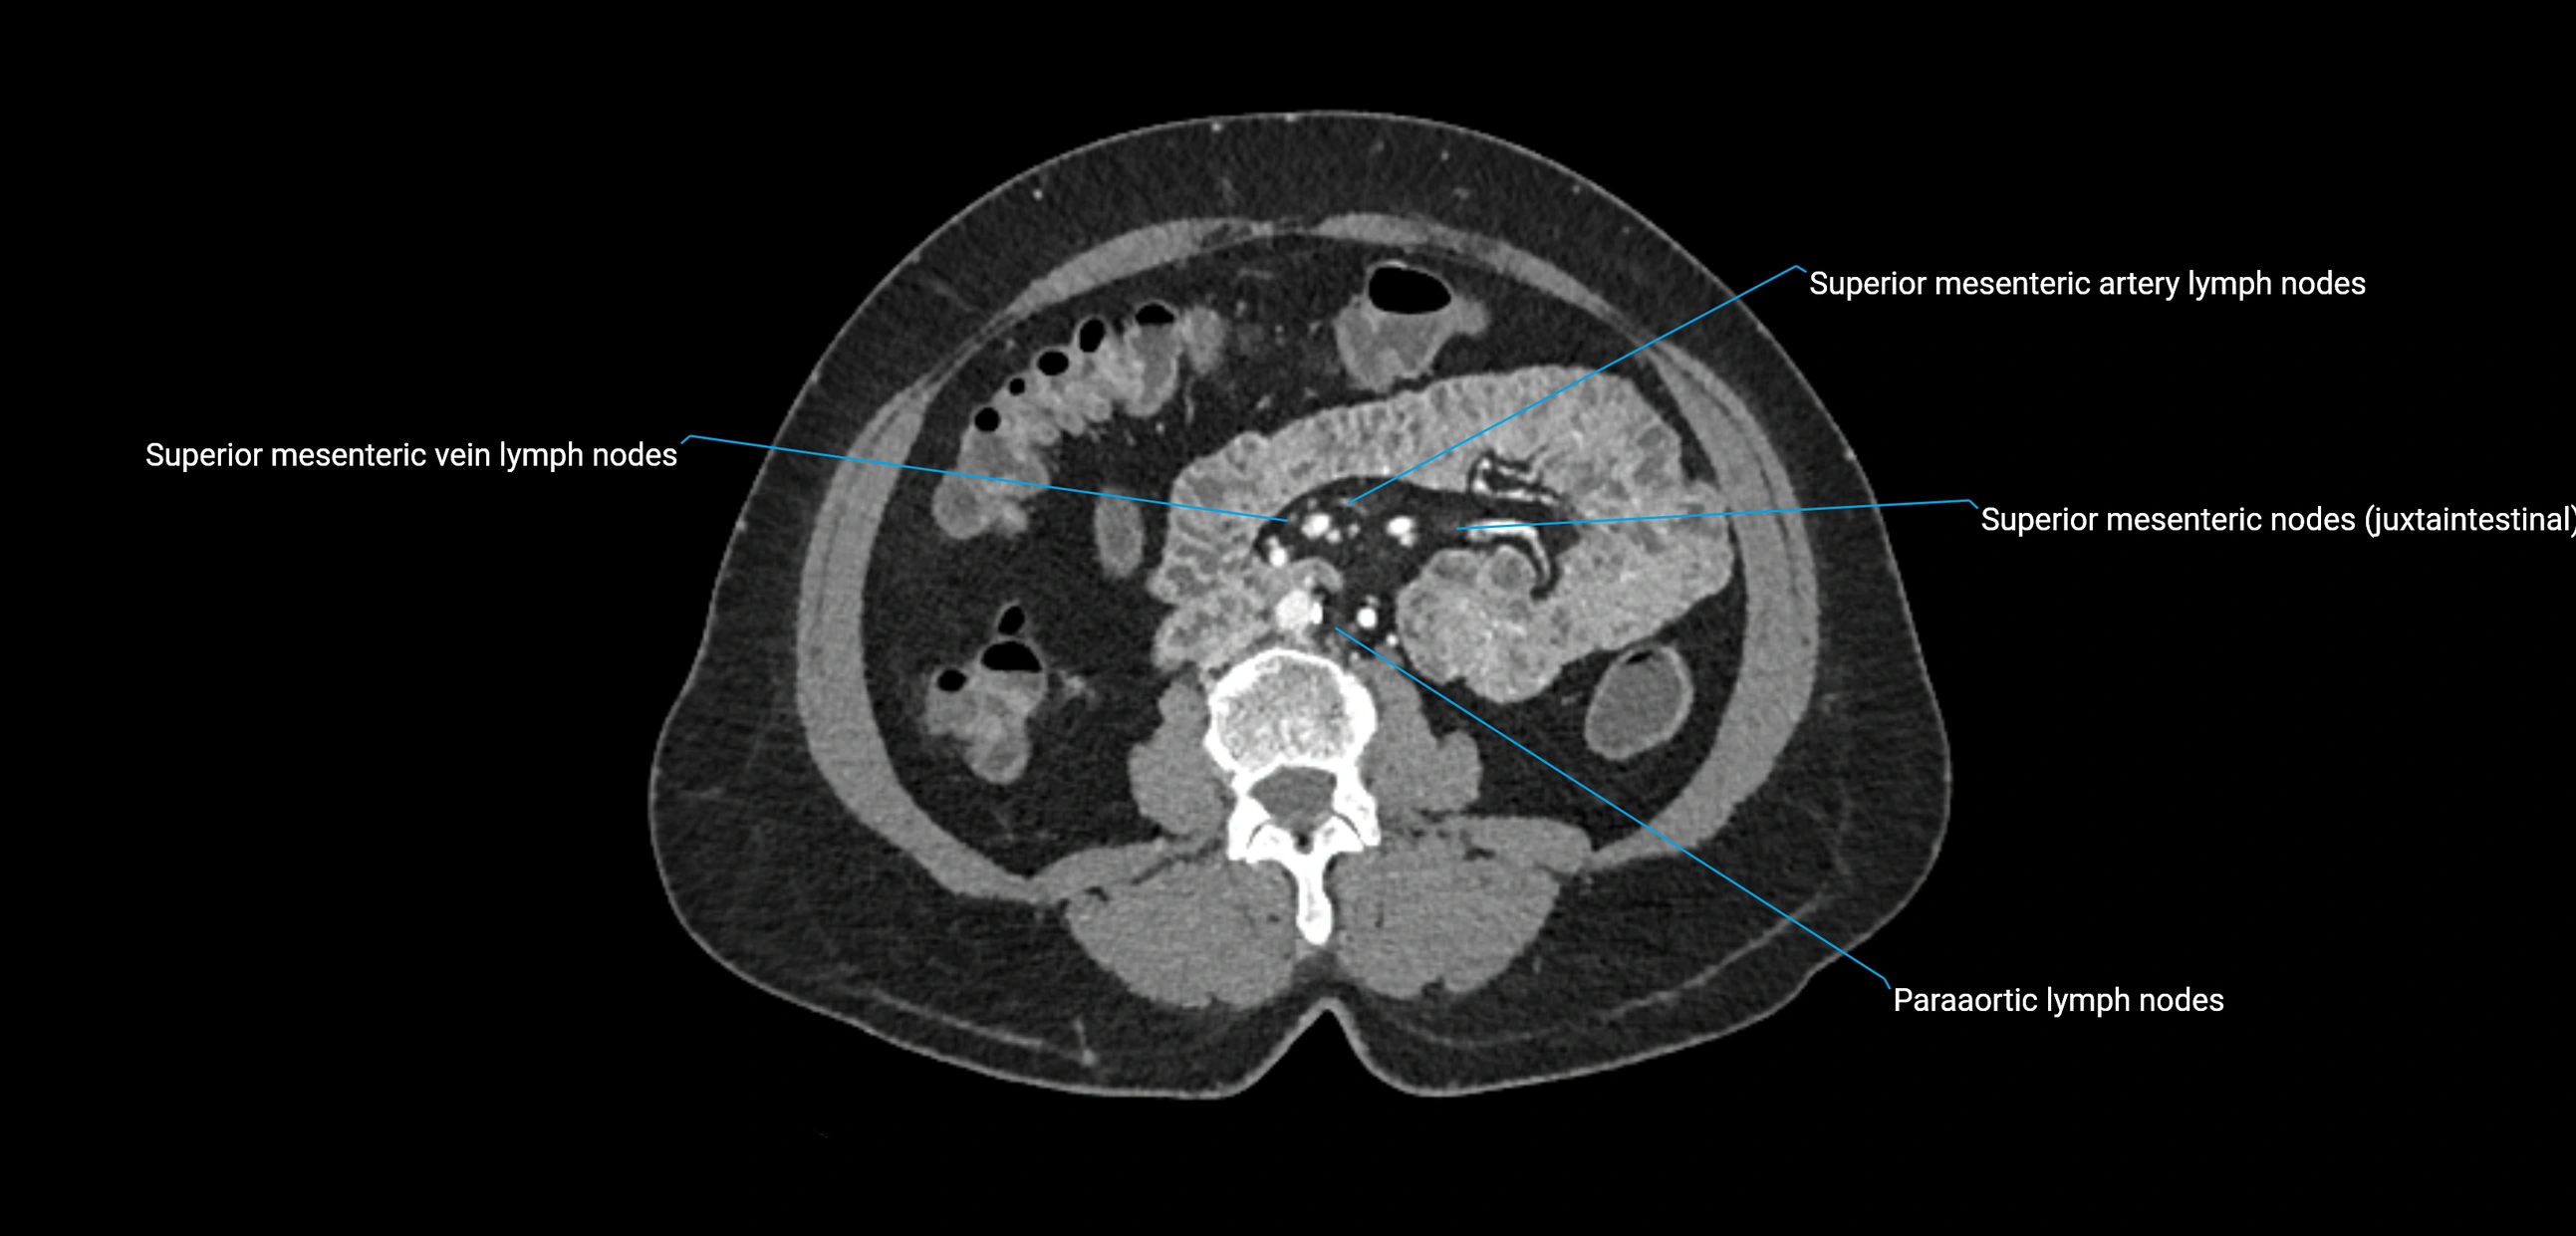

CT Appearance

CT Pre-Contrast:

• Nodes appear as soft-tissue density nodules adjacent to the aorta and IVC

• Calcification may be seen in chronic infections (e.g., tuberculosis)

CT Post-Contrast:

• Normal nodes enhance homogeneously

• Malignant nodes may show heterogeneous enhancement, central necrosis, or conglomerate formation

• Size >1 cm short axis is suspicious, though morphology and distribution are equally important

CT Venography (CTV):

• Demonstrates nodal encasement or compression of adjacent vessels (aorta, IVC, renal veins)

• Useful in staging testicular and ovarian malignancies

• Provides 3D reconstructions for retroperitoneal lymph node dissection planning